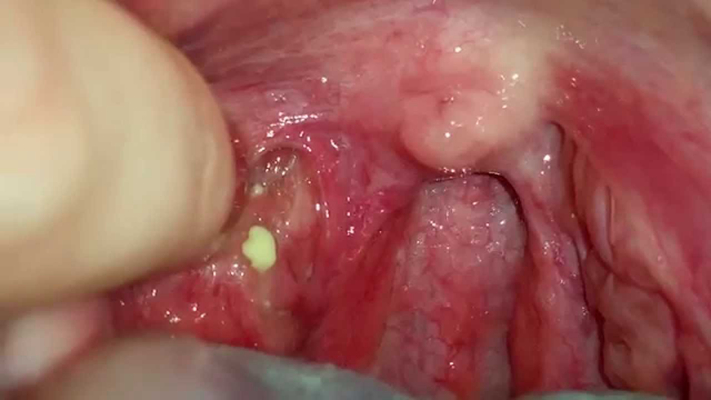

扁桃體結石

扁桃體結石

扁桃體結石

扁桃體結石

扁桃體結石

扁桃體結石

扁桃體結石

扁桃體結石

扁桃體結石

扁桃體結石

扁桃體結石

扁桃體結石

扁桃體結石

扁桃體結石

扁桃體結石

扁桃體結石

扁桃體結石

扁桃體結石

扁桃體結石

扁桃體結石